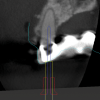

Fig 6: CBCT imaging of a maxillary lateral incisor requiring root canal treatment.

Figure 6

Fig 7: Fusion of CBCT data (shown in magenta) with the IOI (shown in cyan).

Figure 7